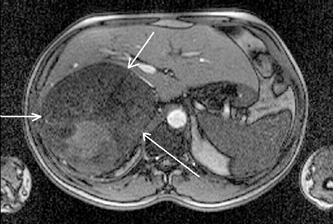

По данным различных авторов, точность ангиографической диагностики опухолей надпочечников составляет 78–95% (Kohler R. et al., 1976; Zografos G.C. et al., 1994). При правосторонней локализации опухоли, особенно больших размеров, для выявления взаимосвязи с нижней полой веной необходимо выполнение нижней каваграфии, желательно в двух проекциях (рис. 5, 6).

Рисунок 5. Нижняя каваграфия (прямая проекция) — сужение и сдавление нижней полой вены опухолью правого надпочечника

Рисунок 6. Нижняя каваграфия (боковая проекция) — оттеснение кпереди и сужение нижней полой вены опухолью правого надпочечника

С начала 80-х гг. XX в. в клинической практике появился принципиально новый метод диагностики — МРТ, основанная на явлении ядерно-магнитного резонанса (рис. 7, 8, 9).

Рисунок 7. МРТ (горизонтальная проекция) — опухоль правого надпочечника

Рисунок 8. МРТ (сагиттальная проекция) — опухоль правого надпочечника

Рисунок 9. МРТ (фронтальная проекция) — опухоль правого надпочечника

Основные достоинства МРТ — неинвазивность, безвредность, трехмерный характер получения изображений. Однако этот метод является одним из самых дорогостоящих, и о применении МРТ при опухолях надпочечников существуют разноречивые мнения. По мнению Nakao Y.et al. (1993), МРТ перспективна для выявления опухолей малых размеров, а Н. Лавин (Эндокринология, 1999) считает, что МРТ в некоторых случаях дополняет результаты КТ, но при малых размерах опухоли надпочечника чувствительность этого метода не превышает чувствительности КТ. Однако, несмотря на использование различных инструментальных методов, точный диагноз, особенно при гормонально-неактивных опухолях, позволяет установить лишь морфологическое исследование, которое возможно при исследовании материала, полученного при аспирационной тонкоигольной биопсии под контролем УЗИ или КТ (Giron J., 1997; Petronio R., 1985) (рис. 10). Точность метода равняется 80–90% (Gonczi I. et al., 1987).